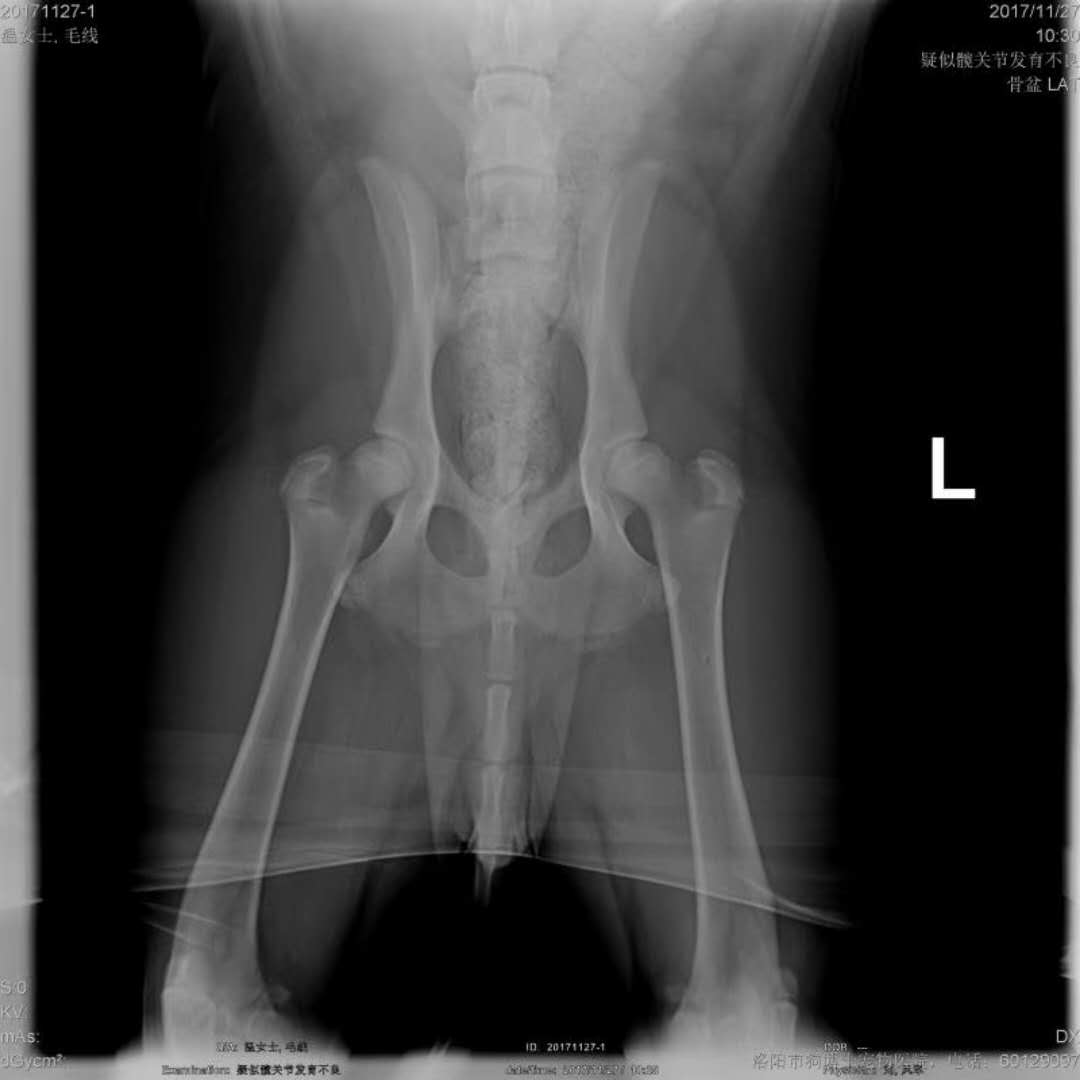

髖關(guān)節(jié)發(fā)育不良病例:金毛,SIRI,近期主人發(fā)現(xiàn)走路或跑動(dòng)時(shí),后肢姿勢異常,不敢用力,偶有疼痛,帶來檢查確診為髖關(guān)節(jié)發(fā)育不良,帶藥保守治療中。